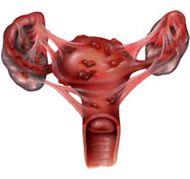

داء البطانة الرحمية بالإنجليزية Endometriosis ، هي حالة مرضية غير سرطانية, و هي عبارة عن ظهور أنسجة بطانة الرحم في أماكن خارج الرحم مثل المبيض , قناة فالوب , المثانة ,الأمعاء , الجلد وغيرها, و تتأثر هذه الأنسجة الهاجرة بالهرمونات التي تفرز من المبيض وخاصة هرمون الاستروجين الذي يؤدي إلى نمو هذه الأنسجة وزيادة سمكها وعندما يقل مستوى الهرمون في الجسم عند اقتراب نزول دم الدورة الشهرية تبدأ هذه الأنسجة بالنزيف وتؤدي إلى حدوث التهابات و التصاقات وعند وجودها في المبيض تؤدي إلى تكوين أكياس دم تسمى أكياس الشوكولاته (chocolate cyst). ويؤثر هذا المرض على 10-15 % من النساء في سن الخصوبة ويعتبر من الأسباب الشائعة لحدوث العقم و آلام الحوض حيث وجد إن 35-50 % من النساء المصابات بهذا المرض غير قادرات على الإنجاب وذلك من خلال تأثيره على المبيض بوجود أكياس الدم اوعندما يسبب المرض الالتصاقات في الحوض و حول قناتي فالوب.